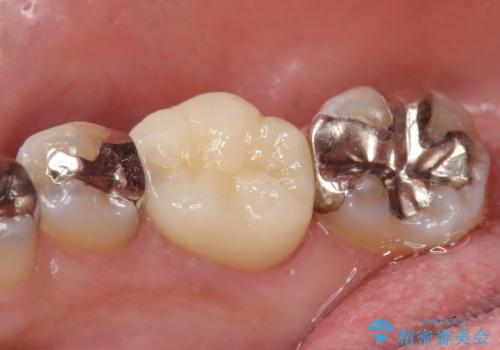

今回用いたオールセラミッククラウンはジルコニアフレームという白い素材の上にセラミックを盛っているため、審美性が非常に高いのが特徴です。

また、ジルコニアは人工ダイヤモンドの材料にも使われているほど高い強度を持っており、そのためオールセラミッククラウンは審美性だけでなく、奥歯やブリッジの補綴も可能とするクラウンです。